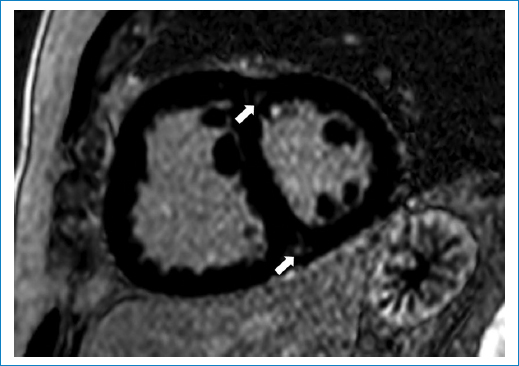

En cuatro pacientes del grupo HP se observó movimiento anormal del TIV con curvatura hacia la izquierda en diástole, no encontrándose este hallazgo en los pacientes del grupo control (control 0 pacientes con y 9 sin movimiento anormal vs. HP 4 pacientes con y 5 sin movimiento anormal; χ2: 5,14; p < 0,05). Asimismo, en tres pacientes del grupo HP se encontró realce tardío intramiocárdico en los puntos de inserción del VD en VI (Fig. 3) no encontrándose este hallazgo en el grupo control (control 0 pacientes con y 9 sin realce tardío intramiocárdico vs. HP 3 pacientes con y 6 sin realce tardío intramiocárdico; χ2: 3,6; p < 0,05).

En casi la mitad de los pacientes se evidenció curvatura del TIV hacia la izquierda en diástole. Roeleveld et al. demostraron que en la HP la presión sistólica de la AP puede superar los 67 mmHg cuando se observa curvatura hacia la izquierda del TIV, encontrándose la máxima distorsión del septum durante la fase de relajación del VD y que la curvatura del TIV se relacionó de forma inversa con la presión del VD11. Los sitios de inserción del VD en VI son regiones sometidas a estrés mecánico, incluso bajo condiciones fisiológicas normales, que se amplifican con la elevación de la presión del VD generando un gradiente de presión transeptal hacia la izquierda. El estrés mecánico de la pared sería el precipitante de la fibrosis focal del miocardio12, observado por la RMC como retención tardía de gadolinio en dichas regiones, hallazgos presentes en el 33% de nuestra serie. Hay estudios que muestran que la extensión del realce tardío intramiocárdico en estas regiones son directamente proporcionales al VTD, masa del VD y presión de la AP e inversamente proporcionales a la FE del VD13. En el presente trabajo, si bien el grupo HP presentó aumento del VTD con disminución de la FE, solo en tres pacientes se observó realce tardío intramiocárdico en sitios de inserción del VD en VI, hecho que podría indicar que este es un signo tardío de HP.